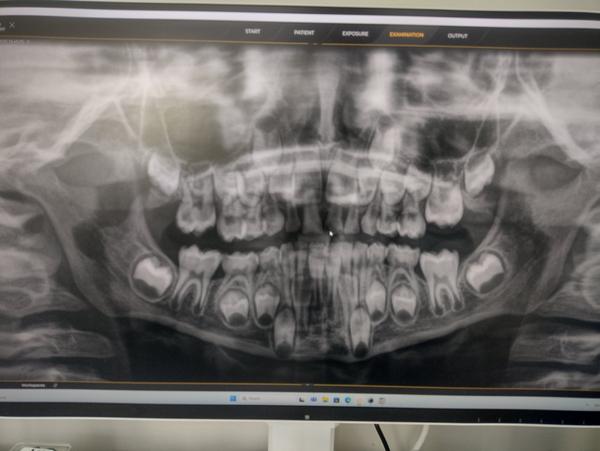

@kaca222 nie som zubar, ale foto RTG som si urobila 😀 ze co vsetko maju deti v puse... 😀 da sa z toho nieco vycitat?

No tu je dôležité aj klinické vyšetrenie 🙂 ale takto z popisu (a rtg) ja nevidím najmenší dôvod na trhanie, keby sa mi niečo nezdalo, odoslala by som vás na konzultáciu k celustnému ortopédovi a postupovala podľa neho.